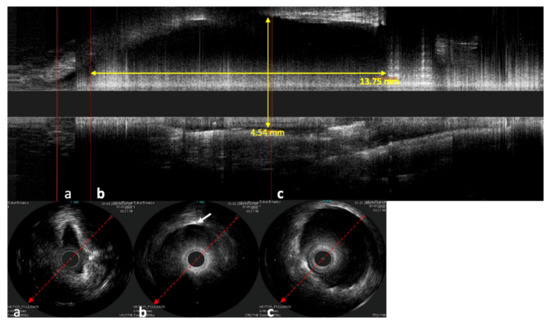

In the longitudinal view, not only can the stent shape be investigated but also how the mucosa of the ET lies around the stent and the position of the stent in the lumen of the ET (Figure 8). In one case, the catheter was next to the stent and not inside of the stent lumen. The stent struts were clearly visible next to the probe in the ultrasound image. Damage to the probe or the stent could not be detected in this case.

Figure 8. Sonographic image of the stented ET, performed with the Refinity ST probe. The upper image shows the longitudinal view of the scan. Parts (ac) show the respective cross-sections of the scans. Part (a) shows the area in front of the stent, where the tubal lumen widens toward the stent. Part (b) shows the initial area of the stent where the first stent strut can be seen sonographically (indicated by white arrow). Part (c) shows the cross-section in the middle section of the stent. The cross-section here was measured to be 4.54 mm. In the longitudinal view, a length of 13.57 mm was measured.